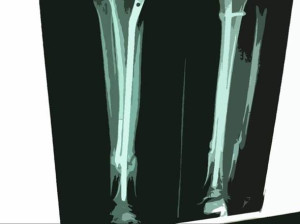

それは、代表(木村)が大きなバイク事故に遭った日でもあります。

事故によって身体のあちこちに後遺症が残り、

当たり前のように歩いていた毎日が突然、遠くなりました。